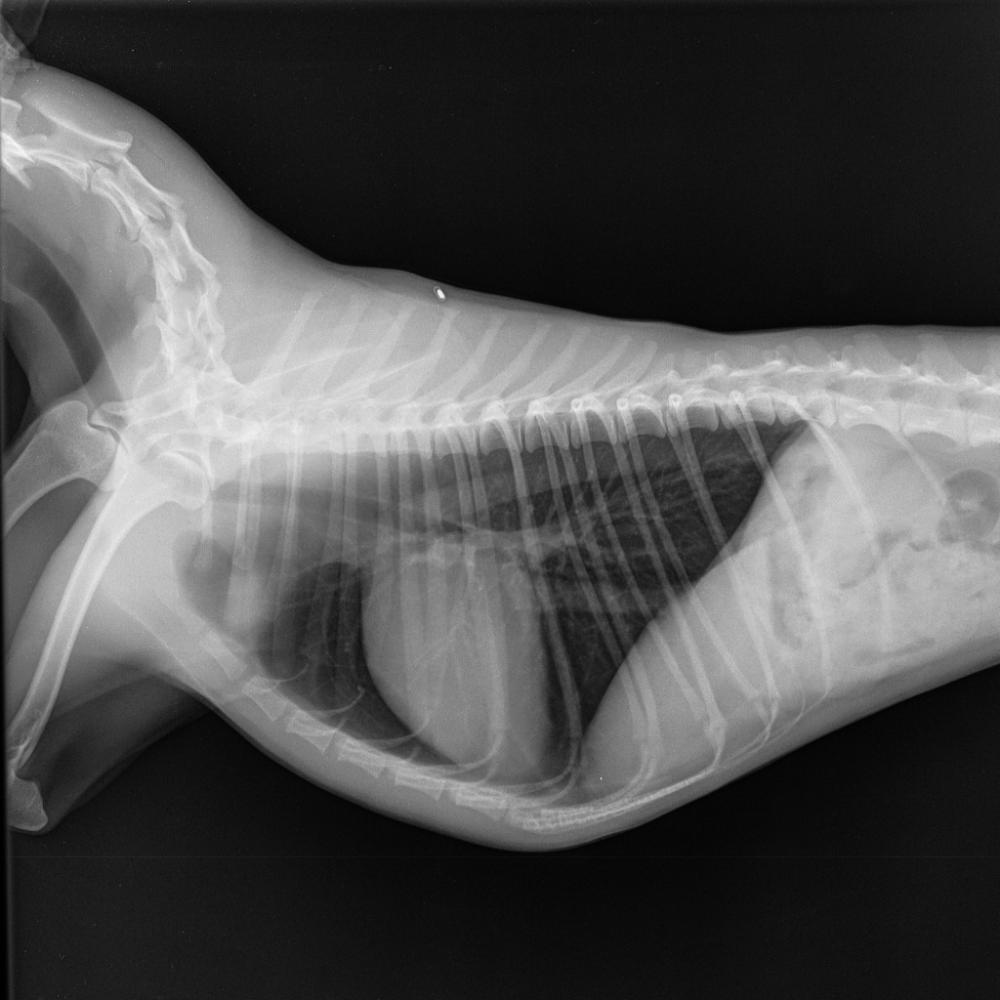

Внучка Опубликовано 18 февраля, 2022 Опубликовано 18 февраля, 2022 Собственно, я уже проконсультировалась и с нашим кардиологом через Ю.П., и с самой Ю.П. Все втроем мы приняли решение прорываться к Бокареву. У него очень забит график, свободные даты только после 5 марта, но нам надо. Очень надо. Можно еще к Комолову, но он тоже весь февраль не принимает - отпуск. Теперь причина. Нормальное сердце (рентген, боковая проекция) Сердце Ники (рентген, боковая проекция) Сердце Ники занимает все пространство грудины, практически лежит на ней. Это создает перегрузку в работе. И тут надо обратиться к тому специалисту, который имеет светлую голову и большую практику. Надо не ошибиться с диагнозом. Спасибо Свете ostorozno -она прорвалась на прием к Бокареву в Одинцово и согласилась еще дополнительно в конце рассказать наш случай доктору. Я буду на связи, возможно,это даст нам назначить дату приема, может, на время до него скорректируют терапию. Мы уже стольких подняли, столько переработали инфы, что у нас просто лозунг "вижу цель, не вижу препятствий". 16